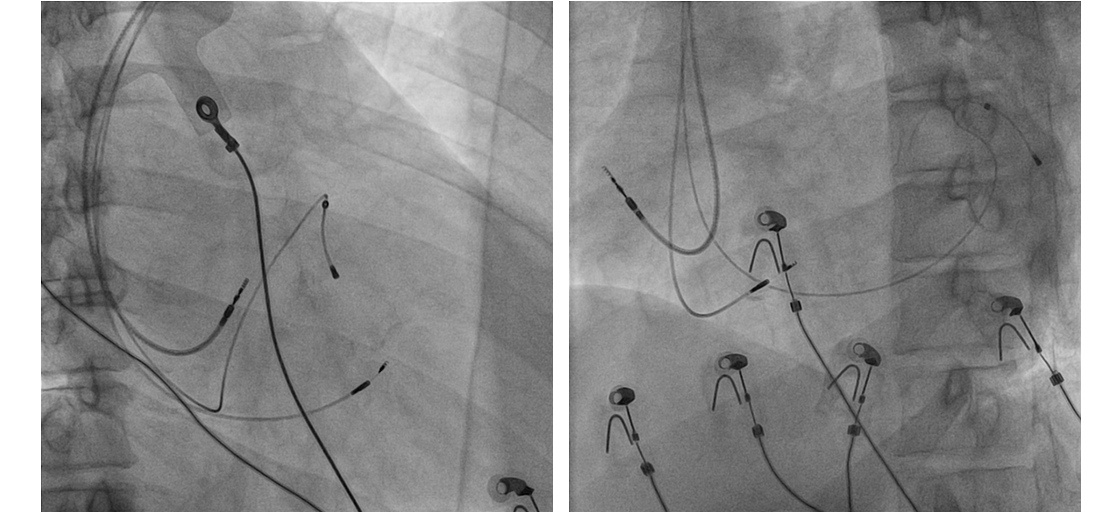

Left bundle lead in place

LB_lead.jpg

Final position

final_position.jpg